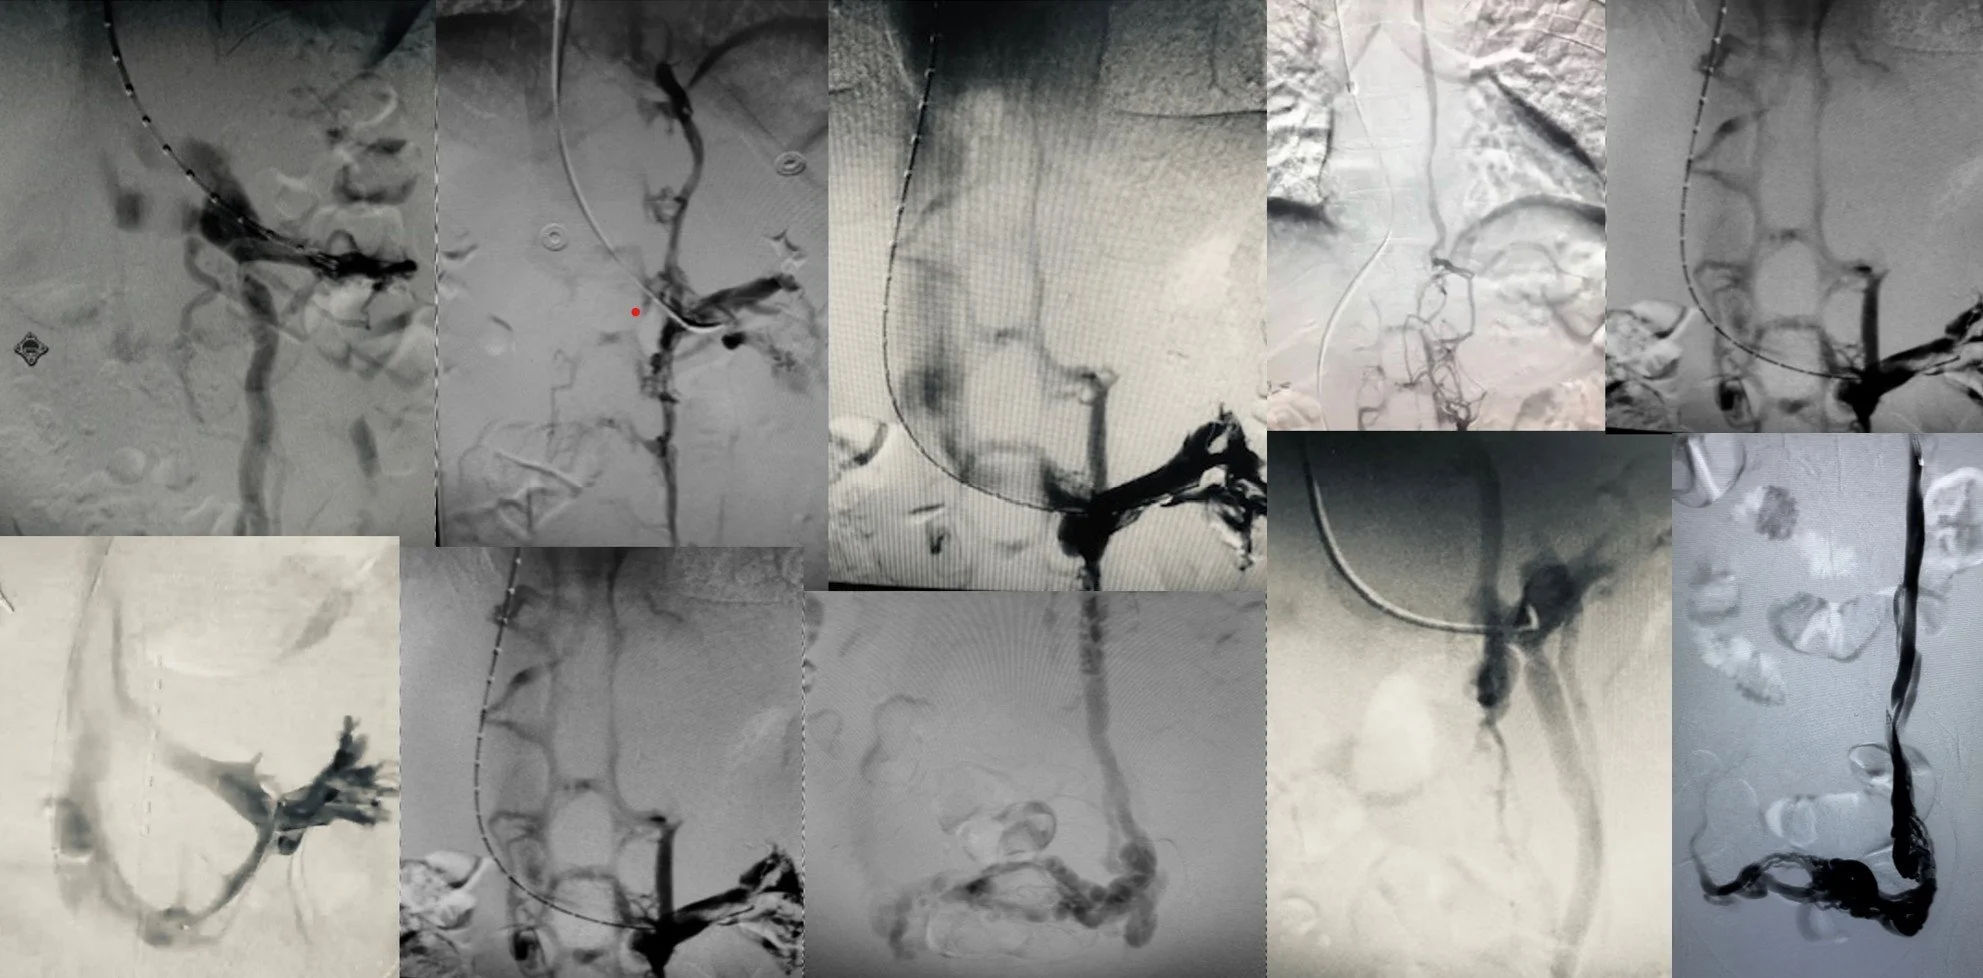

Many faces of Nutcracker Syndrome Venograms Each Presenting with Different Sets of Symptoms